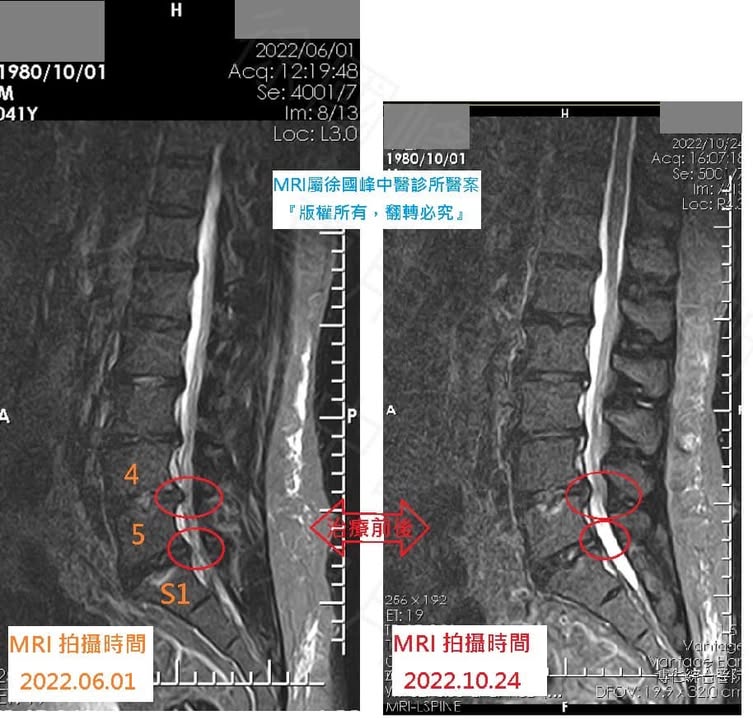

★拍攝MRI在不同切面比對後讓患者更有信心

🌟同一家醫院拍攝MRI比對後,骨科一般都會認為不可能有這種結果

「先說結論,椎間盤突出會不會吸收,會!!但不是每一個人都有這種效果,但是如果患者接受完治療後,症狀已經全部消失,然後再去同一家醫學中心安排核磁共振後,結果出現以下的場景」